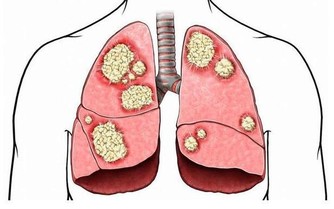

如放療、化療時,配合食補,往往能提高機體對化療、放療的耐受力,保護骨髓功能或促進骨髓功能恢復,改善造血作用,協助放療、化療發揮更大的作用。再者,許多食物本身亦有抗腫瘤的作用,如魚腥草、姬松茸、核桃、等。

提取物之一姬松茸:能增強骨髓造血功能,使外周血的血紅蛋白,血小板及白細胞明顯升高,增強對進行放療和化療的患者的敏感性和耐受性,減少毒副作用,還能增強人體免疫力